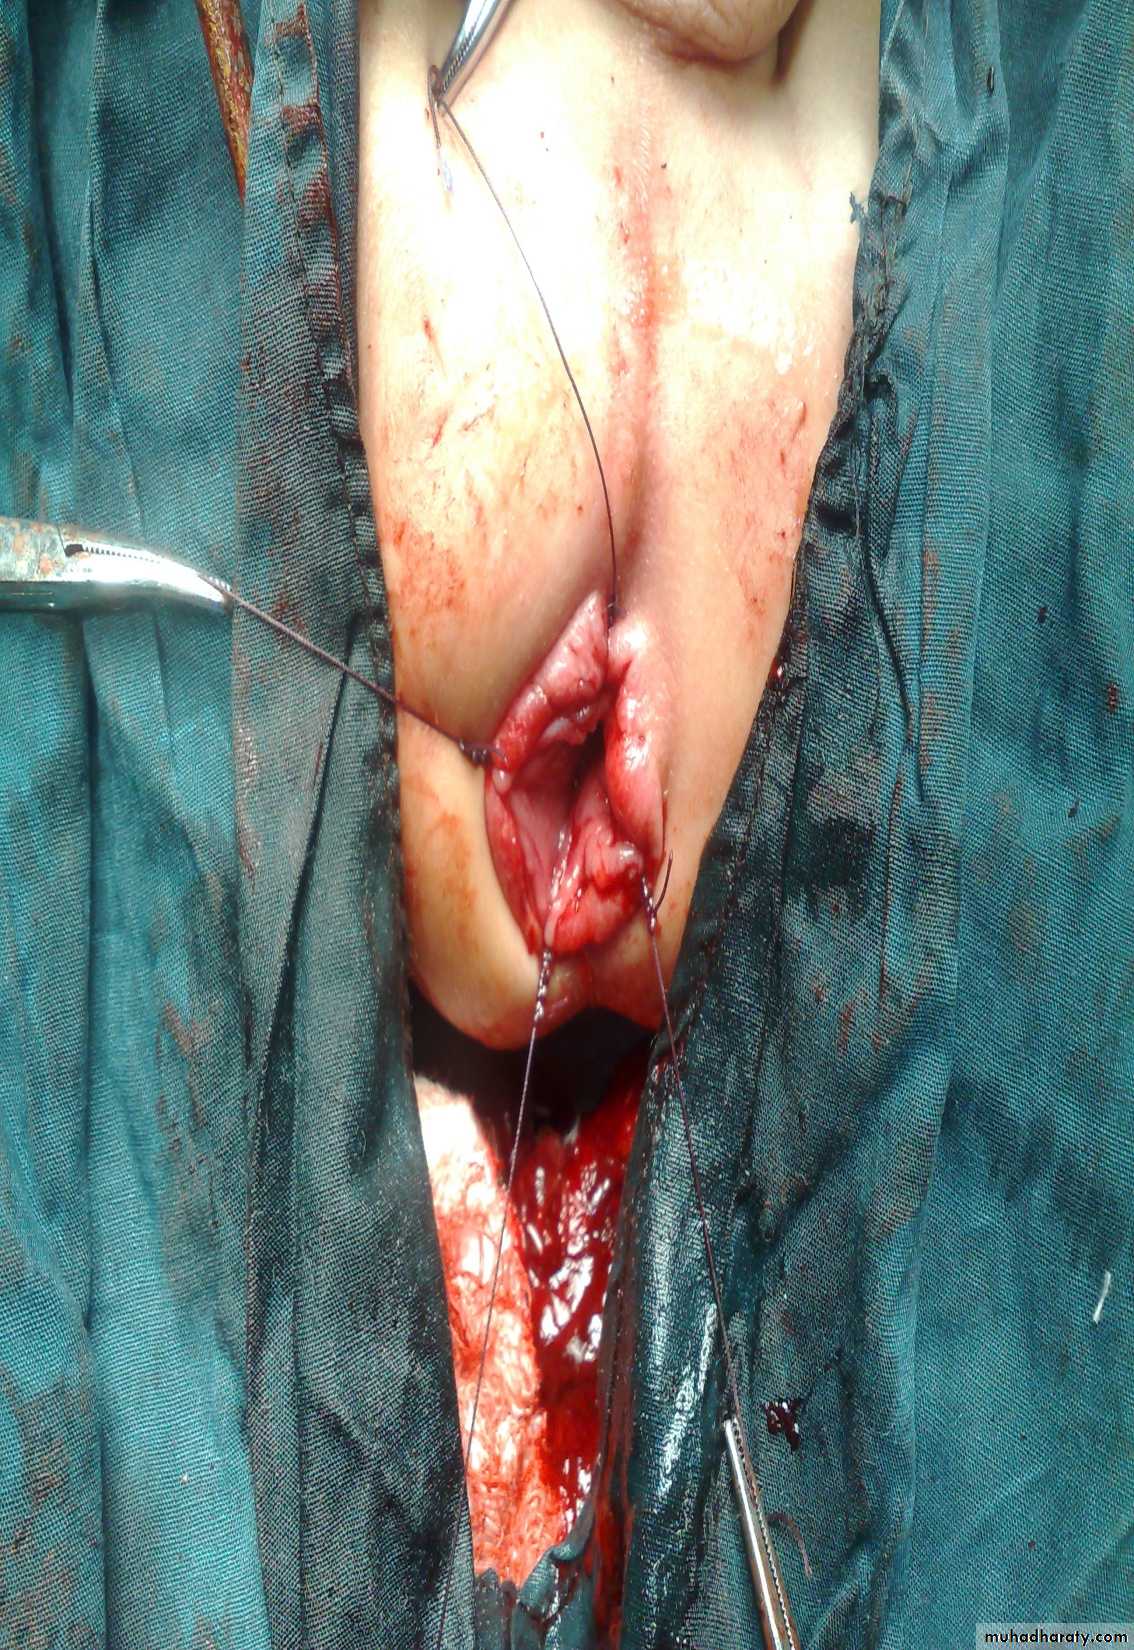

Subcostal incision

Defect=sac

plication